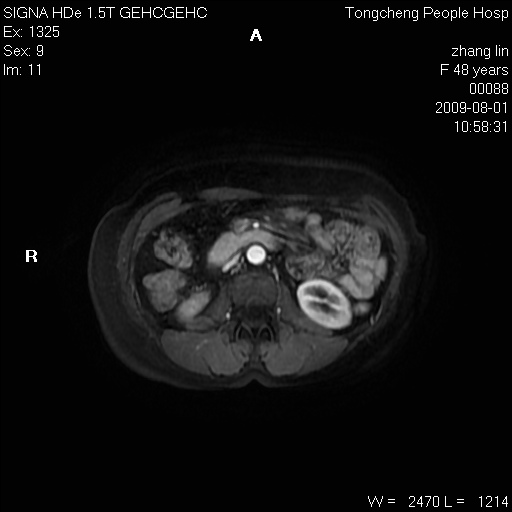

女,48岁。健康体检,彩超发现右肾占位性病变。平素健康。

临床诊断:右肾占位性病变,性质待定(囊肿?肿瘤?)。

上中腹部mr平扫+增强扫描,图像如下:

右肾上极见一类圆形病灶,t1wi呈等信号t2wi呈等高混杂信号,三期增强无强化,边界清---考虑囊肿出血。

同反相位均表现为等信号,病变无强化,考虑含蛋白的囊肿可能,弥散加权相或许有些帮助,